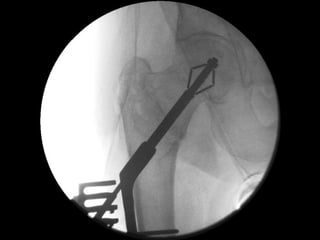

Perpendicular Expansion = No Disruption

Compacts bone = better stability

‘Tip-Apex’ fixation maintained